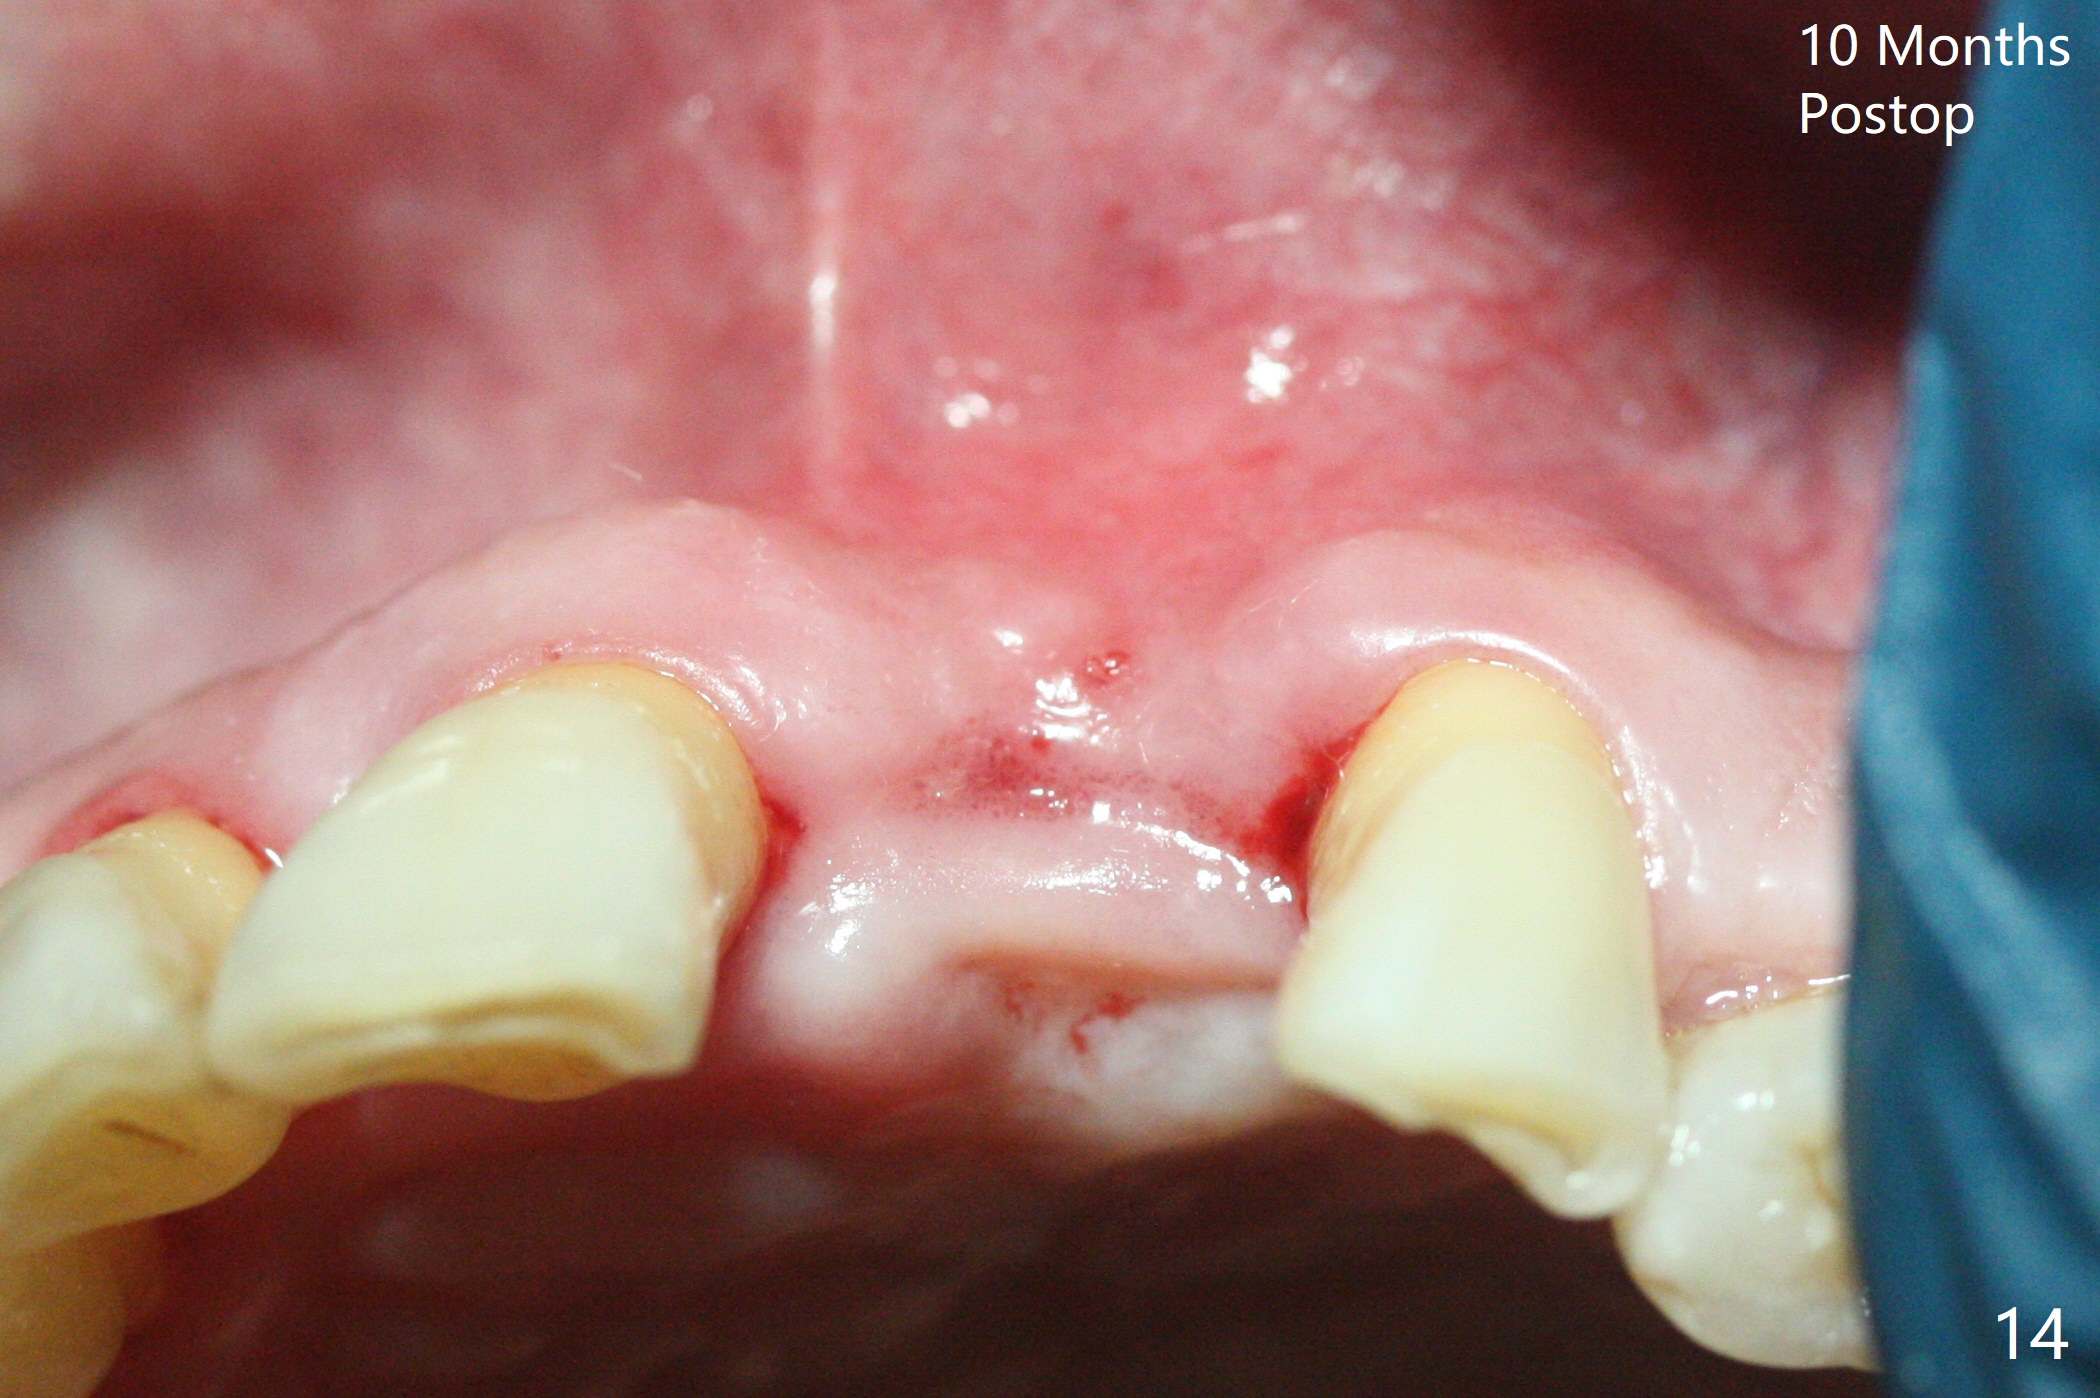

A 67-year-old man requests extraction of the loose tooth #9 (Fig.1). After extraction, the labial plate is found to be missing. With incision, allograft is kept in place with a 12x24 mm anterior narrow Cytoplast and 4-0 Chromic gut suture (Fig.2). Periodontal dressing dislodges in 2 days. The wound dehisces transversely 5 days postop (Fig.3 arrows), whereas the wound was open buccopalatal when the sutures were placed. Probably due to extensive dissection, the erythematous mucosa is large (Fig.4), although asymptomatic. When X-ray shows V-shaped bony defect (Fig.1 (PA), 5 (Pan), 6 (CT)), do not dissect the overlying thin buccal gingiva, which is most likely to dehisce. In fact immediate implant with guide appears to be more conservative, since there is no pressure against the buccal gingiva (Fig.7,8). To be more ideally, the implant could be placed more coronally, longer (13 mm instead of 11.5, Fig.9,10) and narrower (3.5 mm instead of 4.0 mm, Fig.11 (red circles: bone graft)).